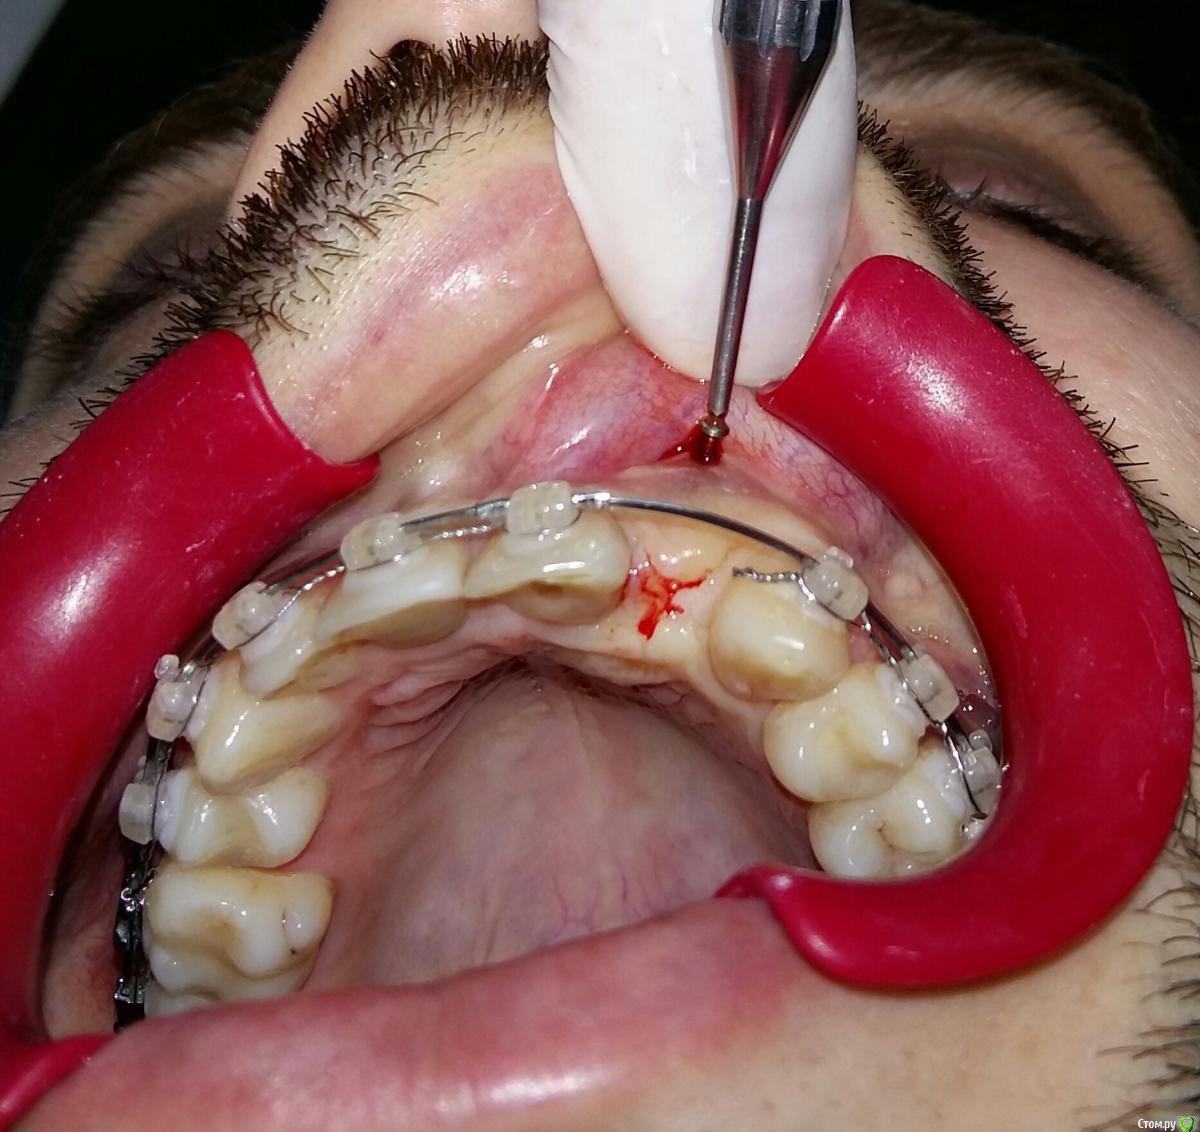

Kostoprav Опубликовано 8 июля, 2015 Поделиться Опубликовано 8 июля, 2015 ИЗНАЧАЛЬНАЯ СИТУАЦИЯ ПОЛУЧИЛОСЬ сори что нет фото до имплантации. Блок взял с тела челюсти, фиксировал двумя винтами (во время имплантации выкрутил только один), присыпал gen os, укрыл дермой-получил заметный прирост слизистой) имплант альфадент 3,75х11,5 2 Ссылка на комментарий

Kostoprav Опубликовано 8 июля, 2015 Автор Поделиться Опубликовано 8 июля, 2015 Видно что блок прирос. ЗдоровоОстальное оценить сложноМне нравится положение импланта в плане оси.Но уровень заглубления не ясенТакже не видно прироста десныВ общем мало данных для оценкиНо опять же вам именно она и нужна?по вестибюлярной поверхности заглубил приблизительно на 1мм с небной больше получилось. слизистая по сравнению с первым разом значительно толще стала, доказать к сожалению не могу так как не делал фото(: я выложил этот пост не только ради оценки, может кому из начинающих данный случай сгодиться 3 Ссылка на комментарий

k.t.m. Опубликовано 8 июля, 2015 Поделиться Опубликовано 8 июля, 2015 Дуга вестибулярная -отличный позиционер вестибуло-)))) 3 Ссылка на комментарий